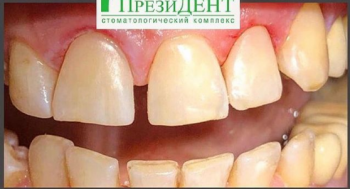

3 работы в портфолио